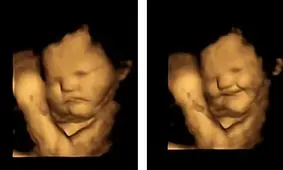

آزمایشی که روی جنینها درون رحم انجام شد، نشان داد که آنها نسبت به طعم غذاهایی که مادران میخورند، واکنش نشان میدهند.